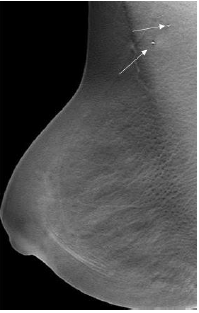

‘Tattoo Sign’- A useful sign in demonstrating the superficial location of skin calcifications. In this sign, the position of the calcifications does not change on multiple views [6] (Figure 1a & 1b).

Figure 1:a) Skin calcifications(arrows) noted in the CC FFDM and DBT view of the right breast of a 50-year-old woman. b) Digital Breast Tomosynthesis images aid in the diagnosis of skin calcifications as they are seen in the first or last three of the images in the stack. Image Courtesy: HCG Hospitals, Bangalore.